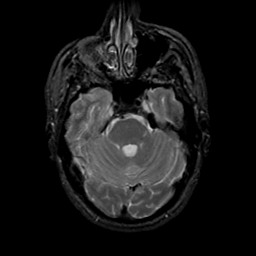

MR Study #19, August 25, 1991 -- Slice #14

[Home][Help][Clinical][Tour 1][Tour 2] Slice 14